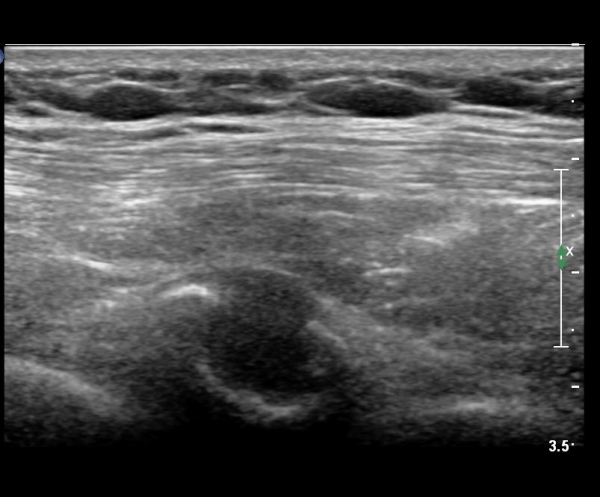

on moving of prove a little, there is bony protrusion(osteoblastic lesion) and hypoechoic(osteolytic)  lesion(image 2, 3, 4).

in transverse scan, visualization of osteoblastic mass with central osteolytic lesion(image 5, 6).

As like this case, visualization of osteoblastic lesion and osteolytic lesion in simultaneously  suggests a malignant mass.